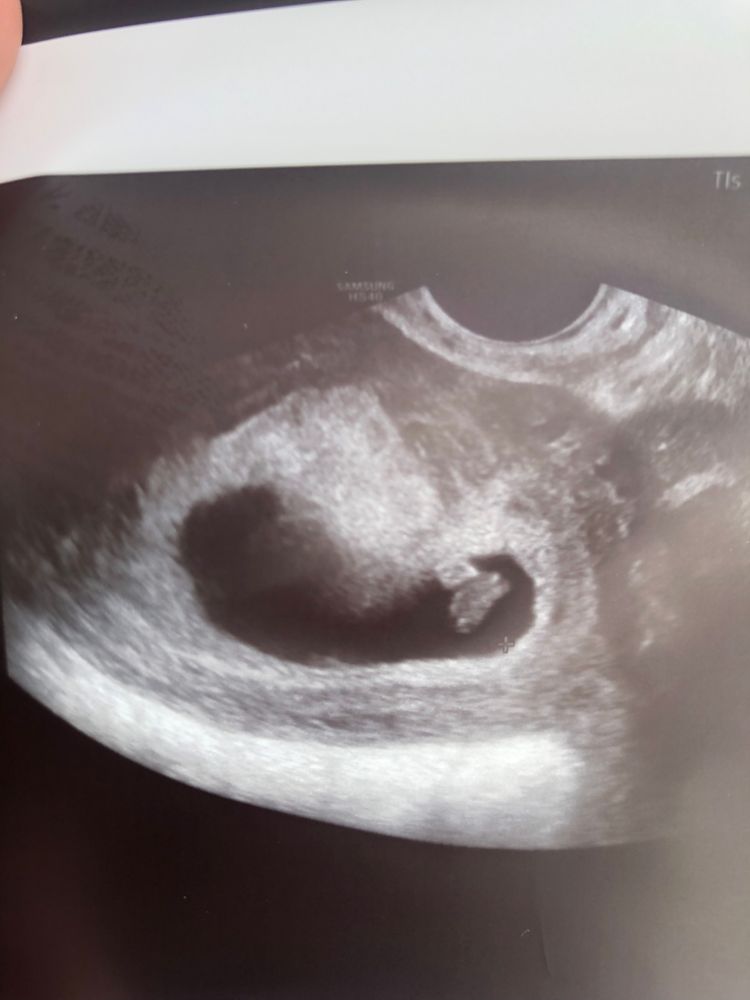

Юлия, 8 недель вот и перегородка в плодном яйце((( Изображение

21.05.2022

bravo gun, у вас ретрохориональная гематома.

Алина, думаете? Это не перегородка?

bravo gun, нет

Вот, нашла ответ врача: «Такого явления, как "перегородка в плодном яйце" не существует. За "перегородку" часто ошибочно принимают амнион, т.е. амниотическую оболочку (мембрану) плодного яйца (это норма); иногда подобная картина наблюдается при наличии ретроамниальной гематомы (как результат частичного отслоения плодного яйца), при этом могут быть кровянистые выделения.»